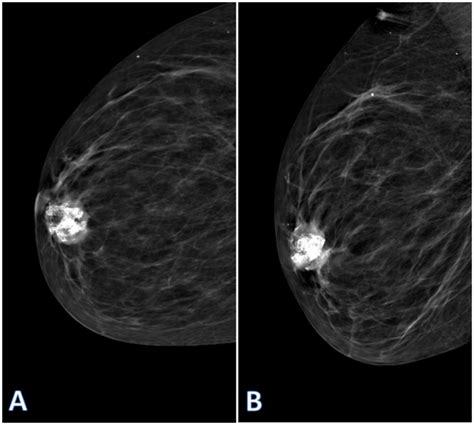

Alright, guys, let’s get down to the nitty-gritty. How does Metaplastic Breast Cancer differ from the breast cancers we hear about more often, like invasive ductal carcinoma or invasive lobular carcinoma? The primary distinction lies in the type of cells involved and their origin. Most breast cancers start in the cells that line the milk ducts or lobules. However, as we touched upon, MBC involves cells that have transformed, or metaplastic , into different cell types. This means that metaplastic tumors are often triple-negative . What does that mean, you ask? It means the cancer cells do not have any of the three common drivers: estrogen receptors (ER), progesterone receptors (PR), or HER2 protein. This is a significant difference because many common breast cancers are hormone-receptor-positive or HER2-positive, making them responsive to targeted therapies like hormone therapy or HER2-targeted drugs. Since MBC is typically triple-negative, these standard treatment options are often not effective. This lack of specific targets makes treatment a bit more challenging and often relies more heavily on chemotherapy. Another key difference is how they appear on imaging. While invasive ductal carcinoma often shows up as a distinct mass on a mammogram, MBC can sometimes appear as a spiculated mass or even be difficult to distinguish from benign conditions like a fibroadenoma, especially if it contains cartilage or bone. This can lead to delays in diagnosis if not carefully evaluated. The rate of growth can also vary. While some sources suggest MBC tends to grow and spread more aggressively than some other types, this isn’t universally true for all cases, and individual tumor biology plays a huge role. However, the potential for rapid growth is a concern that healthcare providers take seriously when managing MBC. The prognosis can also differ. Because of its aggressive nature and triple-negative status, metaplastic breast cancer is often associated with a less favorable prognosis compared to hormone-receptor-positive breast cancers. However, this is a generalization, and many factors, including the stage at diagnosis, the specific subtype of MBC, and the patient’s overall health, significantly impact outcomes. It’s a complex picture, and each case is unique.

Okay, let’s talk symptoms, guys. For Metaplastic Breast Cancer , the symptoms can be quite similar to other breast lumps, but there are nuances to be aware of. The most common sign is a breast lump or mass. This lump is often described as firm, palpable, and sometimes grows relatively quickly. Unlike some slower-growing tumors, MBC lumps can sometimes appear or enlarge more rapidly, which is a red flag. Some women report skin changes over the lump, such as dimpling or thickening, or nipple changes like inversion. Because MBC can sometimes mimic benign conditions, it’s crucial not to dismiss any new lumps or changes. Other potential symptoms, though less common, might include nipple discharge (especially if it’s bloody or occurs spontaneously) or a change in breast size or shape. Remember, feeling a lump doesn’t automatically mean it’s cancer, but it always warrants a professional medical evaluation. The diagnostic process for metaplastic breast cancer often starts with a clinical breast exam, followed by imaging tests. Mammograms and ultrasound are standard initial steps. However, as mentioned, MBC can sometimes be tricky to spot on these initial scans. It might appear as a dense, irregular mass, or sometimes it can be difficult to distinguish from a benign lesion, especially if it has a cartilaginous or cystic component. This is where a biopsy becomes absolutely essential. A biopsy is the only way to definitively diagnose metaplastic breast cancer. A small sample of the suspicious tissue is removed and examined under a microscope by a pathologist. They look at the cell types, their arrangement, and other characteristics to determine if cancer is present and, if so, what specific type it is. For MBC, the pathologist will note the presence of different cell types (epithelial and mesenchymal) and confirm if it’s malignant. Immunohistochemistry (IHC) is a crucial part of this process, helping to determine the hormone receptor status (ER, PR) and HER2 status. As we’ve discussed, MBC is often triple-negative, and the IHC results will confirm this. If a biopsy confirms metaplastic breast cancer, further tests will be done to determine the stage of the cancer (how large it is and if it has spread). This might include imaging scans like CT scans, MRIs, or PET scans. The goal is to get a complete picture of the disease to guide treatment decisions. The diagnostic journey can be stressful, but prompt and accurate diagnosis is the first critical step in effectively managing this rare condition. Don’t hesitate to ask your doctor questions throughout the process; understanding each step is empowering.

It’s also worth noting that the rate of growth of metaplastic breast cancer can vary significantly from person to person. Some tumors may grow quite rapidly, while others might be slower. This variability adds another layer of complexity to diagnosis and treatment planning. When a lump is discovered, doctors will often monitor its growth rate, but if it’s suspicious or growing quickly, a biopsy is usually recommended without delay. The initial interpretation of imaging can sometimes be challenging because metaplastic tumors can have diverse appearances. For example, a metaplastic tumor composed largely of squamous cells might look different on imaging than one with significant chondroid (cartilage) or osseous (bone) elements. This is why the pathologist’s expertise is so invaluable. They are trained to identify these specific cellular components and differentiate them from other breast conditions. The combination of advanced imaging techniques, such as MRI, which can sometimes provide better visualization of complex lesions, and a thorough pathological review is key to achieving an accurate diagnosis. Furthermore, the staging process is critical. It helps doctors understand the extent of the cancer, which directly influences the treatment options and the patient’s prognosis. Staging involves assessing the size of the primary tumor (T), whether cancer has spread to nearby lymph nodes (N), and if it has metastasized to distant parts of the body (M). For metaplastic breast cancer, like other cancers, the TNM staging system is used. Early detection, combined with accurate staging and a precise diagnosis, offers the best chance for successful treatment and improved outcomes.